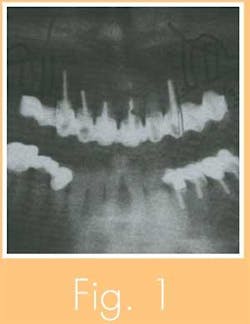

The patient is a healthy, nonsmoking, 50-year-old, white female. She had a 10-unit cantilever bridge spanning teeth 4 through 13, with teeth 6 through 11 as abutments (see Fig. 1).